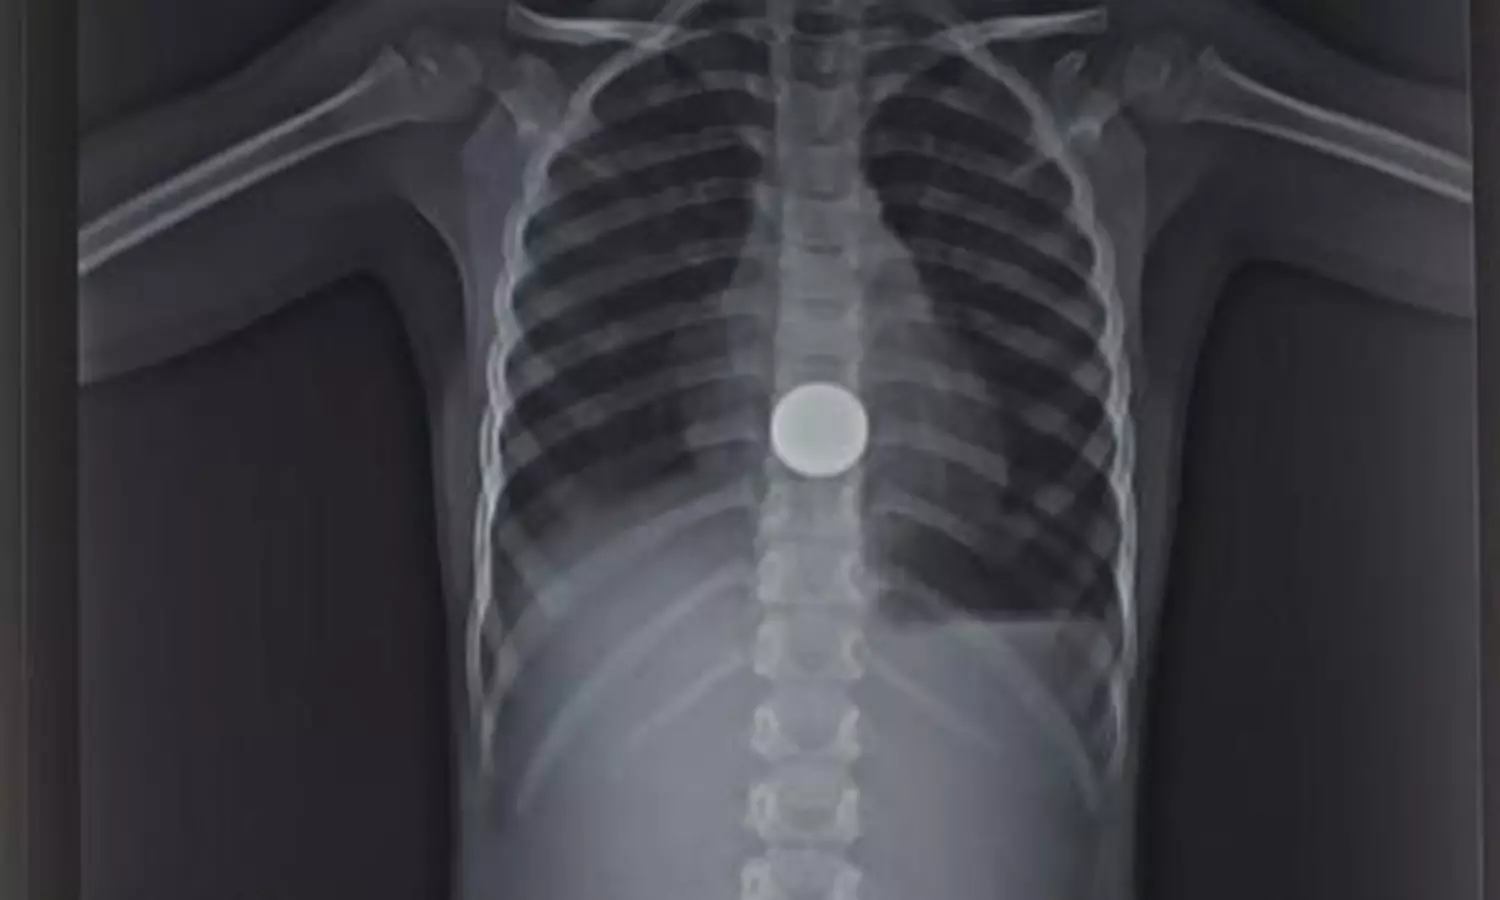

திருப்பூர் மாவட்டம், ஊத்துக்குளி ஒன்றியம், பல்லகவுண்டம்பாளையம் அருகே நேற்று முன்தினம் இரவு வீட்டில் விளையாடிக்கொண்டிருந்த 5 வயது குழந்தை தனது கையில் கிடைத்த 5 ரூபாய் நாணயத்தை வாயில் போட்டு விழுங்கி விட்டாள். நாணயம் தொண்டையில் சிக்கிக் கொண்டதால் அந்தக் குழந்தை தொண்டையைப் பிடித்துக்கொண்டு சத்தம் போட்டு அழுதாள். குழந்தையின் பெற்றோர் உடனடியாக பல்லகவுண்டம்பாளையத்தில் உள்ள ஒரு தனியார் மருத்துவமனைக்கு குழந்தையை கொண்டு சென்றனர். அங்கு குழந்தைக்கு எக்ஸ்ரே எடுத்து பார்த்ததில் உணவுக்குழாயில் 5 ரூபாய் நாணயம் சிக்கி இருப்பது தெரிய வந்தது.

அதனைத்தொடர்ந்து குடல் இரைப்பை அறுவை சிகிச்சை மருத்துவர் மற்றும் மயக்கவியல் நிபுணர்கள் கொண்ட குழுவினர் எண்டோஸ்கோபி சிகிச்சை மூலம் நாணயத்தை வெளியே எடுத்தனர். அவர்களுக்கு பெற்றோர் நன்றி தெரிவித்துக்கொண்டனர்.